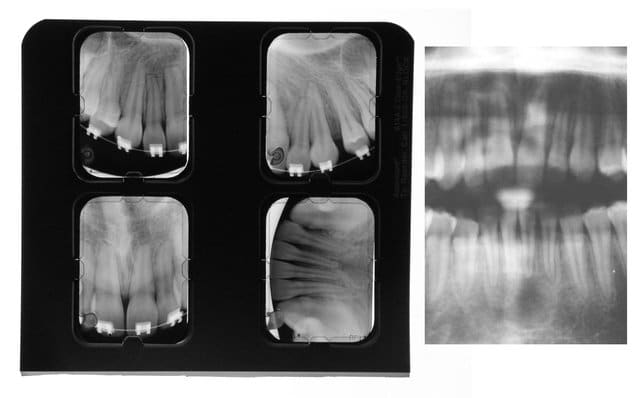

> Et là, peut on parler de rhisalyse? Patient avec

> une superbe occlusion, afmp trés petits et éhgaux

> et je pense que ca le sauve pour l'instant

Cette pano est déformée, à refaire et compléter par un bilan RA avt toute conclusion

Et là, peut on émettre un semblant de conclusion ?